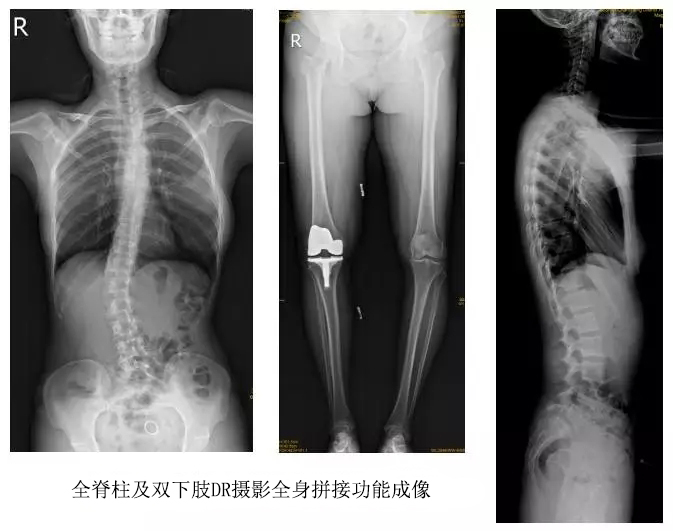

以某院所攝X光片為例,對比傳統(tǒng)攝片與全身拼接功能的區(qū)別:

傳統(tǒng)X光片只能觀察每個部位的局部情況,無法在統(tǒng)一體上進行連續(xù)、全面的觀察,全脊柱及下肢全長片則能直觀的看到整體形變。通過DR全身拼接功能實現(xiàn)的完整成像,為診治脊柱及下肢畸形提供了完美的臨床影像依據(jù),對臨床診斷、術(shù)前手術(shù)方案的制定和術(shù)后療效的評估等臨床應(yīng)用具有十分重要的意義,有效滿足了此類疾病臨床診斷和治療的要求。

通過以上對比,可以發(fā)現(xiàn),在缺少DR全身拼接功能的條件下,傳統(tǒng)X光攝片無法有效解決骨科常見疾病如脊柱側(cè)彎及下肢畸形的臨床診斷。在國家大力推進健康中國、人民不斷增長的醫(yī)療需求的大背景下,醫(yī)療缺陷將不斷被合理技術(shù)替代,因此從對立面評測,如今,沒有全身拼接功能的DR就不是合格的DR。